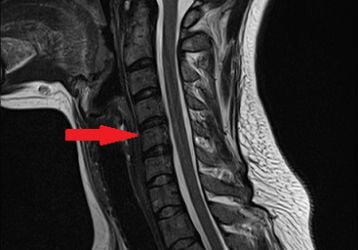

Нарушение мозгового кровообращения при шейном остеохондрозе: лечение, симптомы, причины недуга

Причины развития, симптомы и лечение нарушения мозгового кровообращения при шейном остеохондрозе. Как лечить сосудистые нарушения при остеохондрозе..